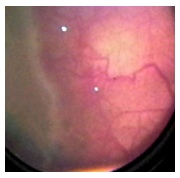

El desprendimiento retinal en la Retinopatía

del Prematuro es de origen traccional y presenta un componente exudativo

asociado. El fluido subretinal suele ser de aspecto sanguinolento

y las áreas de desprendimiento retinal suelen estar demarcadas

por un cambio de coloración y exudados.

Es importante no confundir las zonas de DR con

zonas en las cuales vasos retinales se elevan sobre el plano de

la retina para ingresar al ridge sin existir necesariamente un desprendimiento

retinal, son los denominados “vasos puente”.